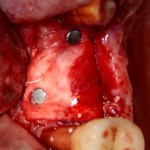

Например, в следующей ситуации:

Оставить так, как есть — это значит, сильно рисковать имплантом и объемом альвеолярного гребня — фактически, большая часть импланта пятого зуба «висит в воздухе». Поэтому получившуюся костную полость мы заполняем аутокостной стружкой в смеси с Bioss и закрываем коллагеновой мембраной BioGide: